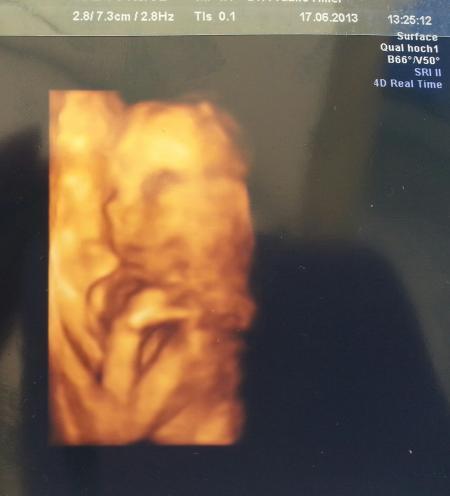

hallo Ihr lieben!!!! .....ist das schön - zurück vom Arzt und so ein tolles Gefühl " in Bauch"!!! Leider konnte mein Mann heute nicht mit, da er zu dieser Uhrzeit (11:00Uhr) natürlich arbeiten muss. Als ich im Wartezimmer ganz vertieft in meine Klatschzeitschrift war, fragte mich jemand, ob neben mir noch ein Platz frei ist.... das war mein Schatz. Hab ich mich so gefreut, er wollte mich einfach überraschen!!! Bei mir hat sie heute das II. Screening gemacht und alles super !!!!! Man konnte sehr schön das Herz und die einzelnen Kammern sehen, den Magen, beide Nieren, die Wirbelsäule, und den Bereich über der Lippe, die kleinen Füßchen usw. Fazit alles in bester Ordnung! Und dann ging die Suche nach dem Geschlecht los..... Es könnte ein Mädchen sein.....mmmmhhhhh....doch doch, also ich sag es wird ein Mädchen - so die Ärztin !!! Aber das endgültige Ergebnis sollten wir uns bei der Feindiagnostik bestätigen lassen. Wir haben süße Bilder bekommen. Die kleine Maus sieht aus, als ob man sie zum Fotoshooting eingeladen hat ( das Kinn stützt sie ganz lässig auf dem Handrücken ab - voll niedlich) Da ich auch in letzter Zeit über Unterleibsziehen klage, hat die Ärztin alles genau untersucht. MM schön fest & geschlossen. Zur Sicherheit dennoch nen Abstrich genommen. Und ich soll auch Nachmittags bzw. Abends nochmal Magnesium nehmen. Nehme es bislang nur Morgens. Wenn sich irgendetwas ändert, soll ich sofort vorbei kommen. (Foto vom Mäuschen sende ich gleich nach) Viiiiiieeeeelllll lieben Dank an Euch alle fürs Däumchen drücken Liebe Grüße sendet Euch der glücklichste Schneehase

Oh wie schön Dein Bericht liest sich ganz toll und das Bild ist super süß

So wie es da liegt und posiert ist das bestimmt ein Mädchen Richtig zucker die bilder :)

Wie es aussieht freut sich die kleine sehr. Ach Gott so ein süßes lächeln